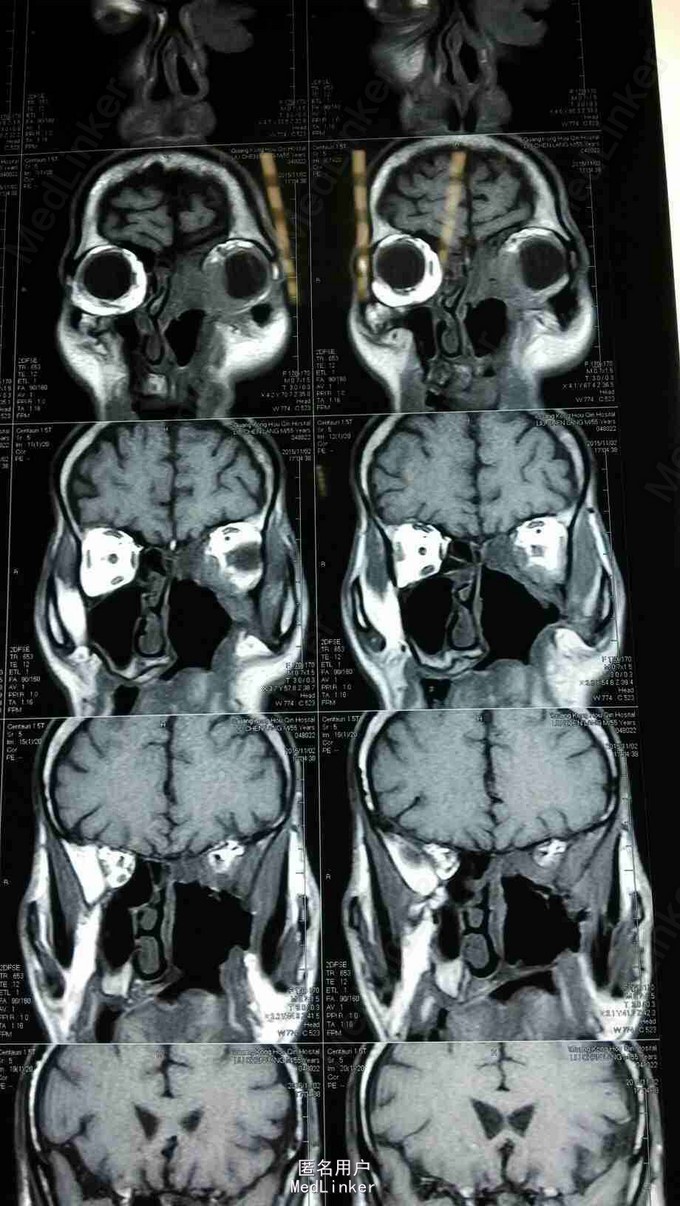

查体:患者神清,消瘦,发音不清,全身浅表淋巴结未见肿大,左眼上睑内侧可见肿物,大小约1*1cm,皮肤红肿,无破溃,质硬,伴压痛,不活动,眼睑闭合不全,睫毛方向正常,眼部可见少量脓性分泌物。 MRI:左侧上颌窦术后改变,左上颌窦顶壁及左眼眶内下方异常信号,考虑肿瘤复发,累及左眶内眦部,前组部分筛窦,内下方肌间隙及上下眼睑内侧份。